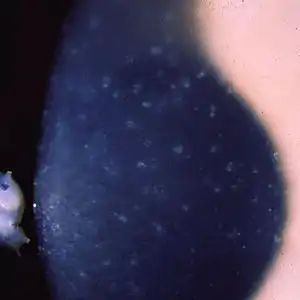

| Multiple opaque spots in the corneal epithelium | |

Patients with Meesmann corneal dystrophy may remain asymptomatic or experience mild symptoms. Symptoms of Meesmann corneal dystrophy often go unnoticed and is usually found and diagnosed during routine eye examinations.[9] This slowly progressive disorder is characterized by microcysts that are filled with debris in the epithelium of the cornea detected and clinically diagnosed with slit-lamp biomicroscopy and retroillumination.[1][10] Under electron microscopy, there are an abnormal aggregation of keratin filament bundles in the center of the cornea.[11] It was found to not affect the corneal stromal layer or endothelial cell layer.[12] Signs of this disease appear in the early first few years of life and begin as eye irritation. Under magnification, corneal changes consisting of punctate opacities in the epithelium are found. Occasionally, these are found in the Bowman membrane. Patients diagnosed with Meesmann corneal dystrophy are unable to tolerate the use of contact lenses which irritate the corneal epithelium. Light microscopy and electron microscopy found that the basement membrane is thickened with an intracytoplasmic substance. Under slit-lamp photography, the cornea was found to be uneven due to the damage and scarring from the thickening basement membrane and anterior stroma. The buildup of foreign materials may cause vision blurriness or cloudiness.[6]